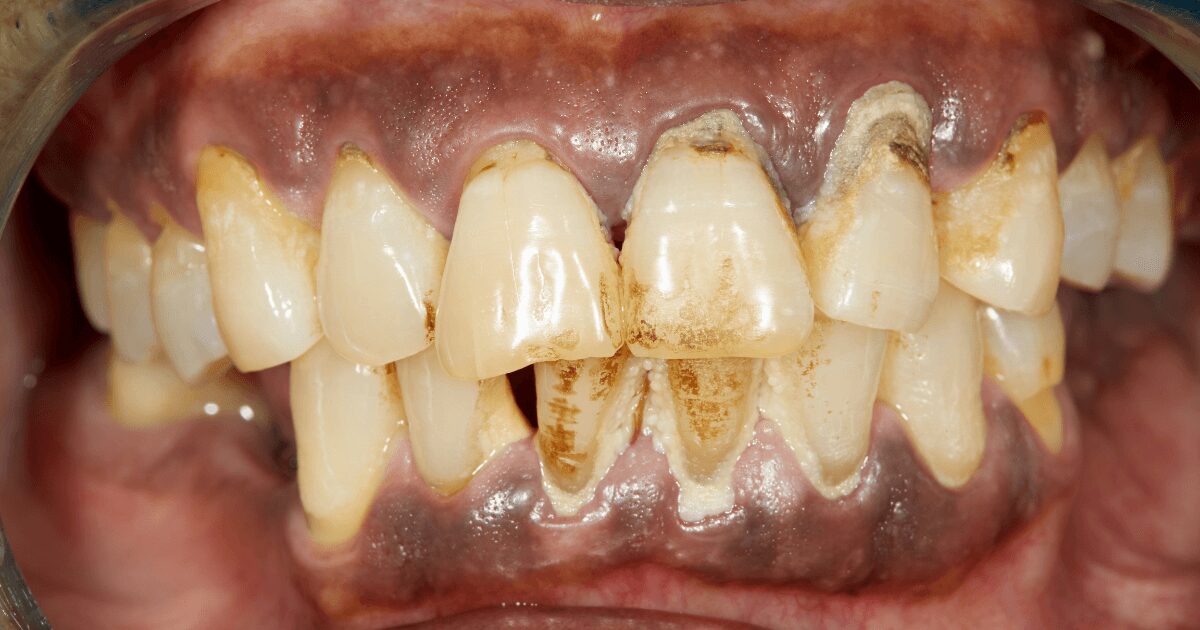

④ 重度歯周病

歯を支える骨がほとんどなくなり、歯が大きく揺れるようになります。

このまま放置すると、最終的には自然に歯が抜けてしまう可能性もあります。

また、歯周ポケットが深くなり、膿がたまって強い痛みを感じることもあります。